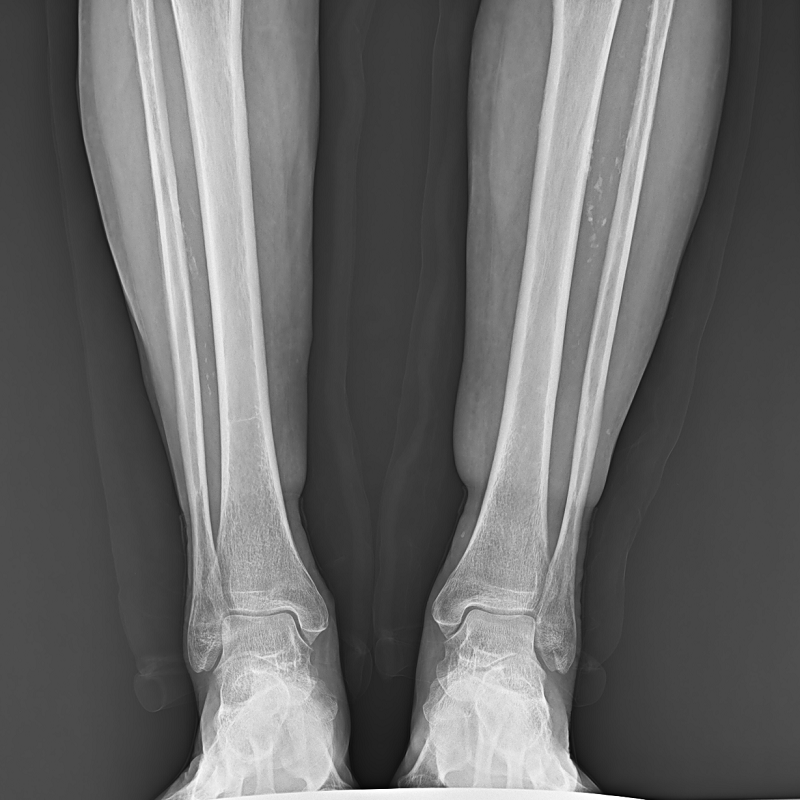

全自動(dòng)拼接

●呈現(xiàn)全下肢或全脊柱圖像

●在脊柱及下肢畸形矯正手術(shù)治療中,為術(shù)前方案制定和術(shù)后復(fù)查提供精準(zhǔn)測(cè)量

●有效解決傳統(tǒng)X光片不能一次成像問(wèn)題,為患者提供更加優(yōu)質(zhì)的醫(yī)療服務(wù)

Clinical picture

臨床圖片